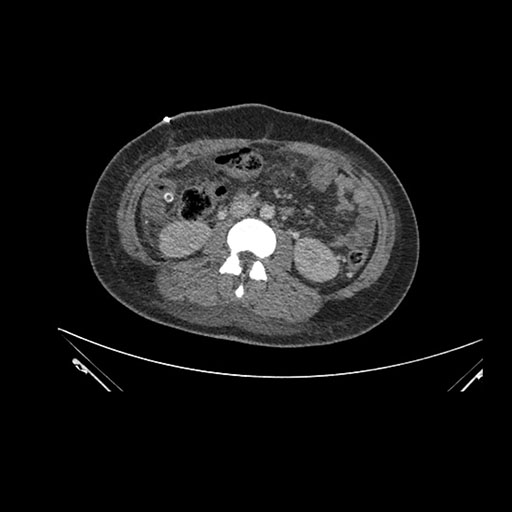

Imaging Analysis

Look through the patient's CT scan to identify any areas of concern for the necessary procedure.

Coronal Arterial

Based on initial findings, which issue(s) would you be most concerned about?